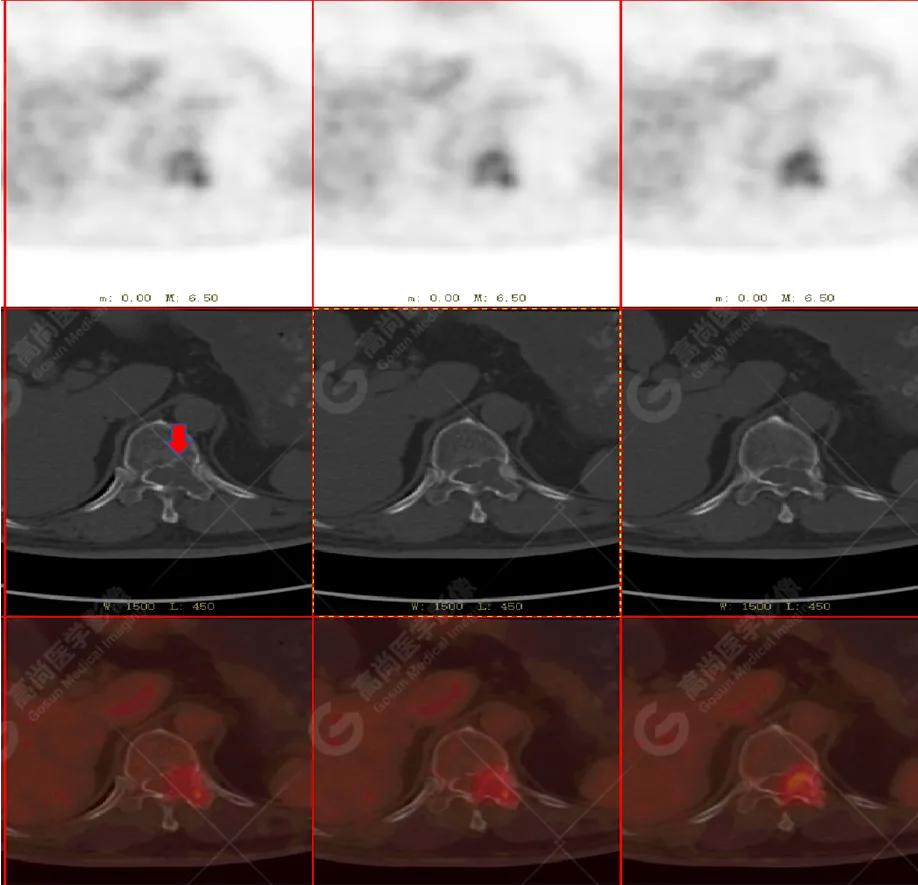

PET/CT

影像图

胸椎溶骨性骨质破坏,FDG环状代谢增高,SUVmax为4.0。

左侧乳腺一软组织结节,FDG代谢增高,SUVmax为2.6。

最终诊断: 左侧乳腺癌伴胸椎单发骨转移。